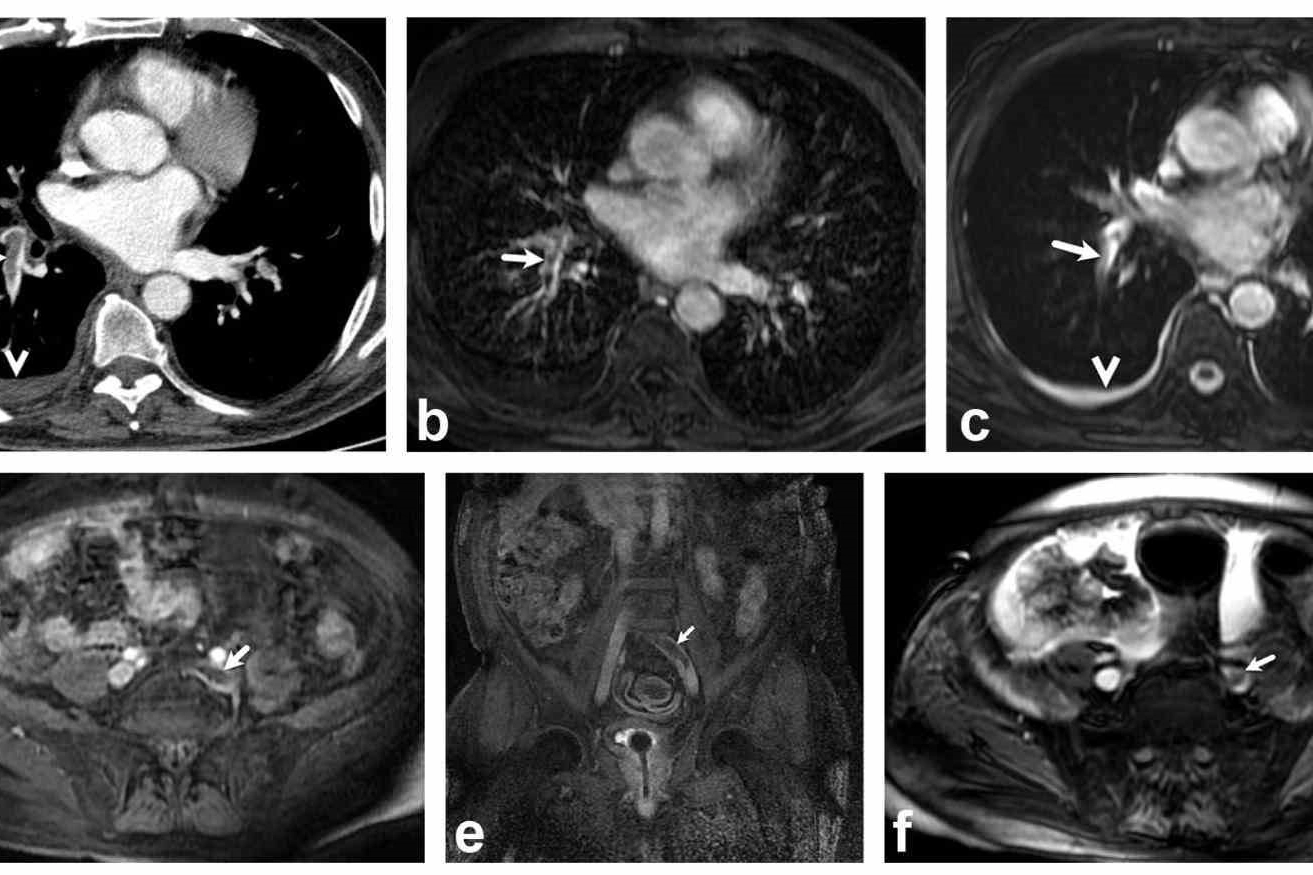

Denizli Tekden Hastanesi’nde görev yaptığı dönemde başarılı çalışmalara imza atan ve kariyerine ABD’de devam eden Radyoloji Uzmanı Dr. Nevzat Karabulut, tıp dünyasında çığır açan bir başarıya imza attı. Dr. Karabulut ve ekibi tarafından geliştirilen, akciğer embolisi ve bacak pıhtılarını aynı anda radyasyonsuz görüntüleyen yöntem, dünya çapındaki prestijli bilimsel dergilerde en güvenilir metotlar arasında gösterilmeye başlandı. Özellikle hamileler ve gençler için hayati önem taşıyan bu yöntem, radyasyon riskini tamamen ortadan kaldırıyor.

2025 yılında yayımlanan ve 2 bin 611 hastayı kapsayan dev bir uluslararası meta-analizde, Dr. Karabulut’un çalışması en güçlü referanslardan biri oldu. Araştırma sonuçlarına göre; geleneksel nükleer tıp yöntemlerinde her üç hastadan birinde (%34,7) net sonuç alınamazken, Dr. Karabulut’un öncülük ettiği MR yönteminde bu hata payı %3,31’e kadar düştü. Bu veriler, MR tekniklerinin pıhtı teşhisinde çok daha net ve yorumlanabilir sonuçlar verdiğini bilimsel olarak kanıtladı.

Hayati tehlike oluşturan akciğer embolisinin teşhisinde genellikle radyasyon içeren Bilgisayarlı Tomografi (BT) kullanılıyor. Dr. Nevzat Karabulut, geliştirdikleri yöntemin önemini şu sözlerle anlattı: "BT anjiyografi özellikle hamileler, genç hastalar ve alerjisi olanlar için risk barındırabiliyor. Ekibimle yaptığımız bu çalışma, hem akciğer damarlarını hem de pıhtının kaynağı olan bacak damarlarını radyasyona maruz bırakmadan tek seferde inceliyor. Çalışmamızın uluslararası büyük araştırmalarda kaynak gösterilmesi, Türk tıbbının başarısını ortaya koymaktadır."